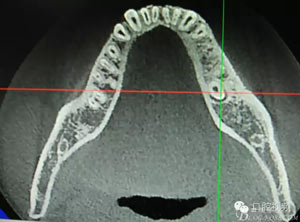

患者、盧xx、男、19歲。主訴:左側(cè)下頜乳磨牙未脫落,要求檢查。??茩z查:左側(cè)下頜第二乳磨牙有充填物。無松動,全景片檢查。35移位至36、37之間。頰舌側(cè)均不能觸及隆起。CBCT檢查:35位于36、37的舌側(cè)。表面骨質(zhì)約2mm左右。35完全骨埋伏,36的遠(yuǎn)中牙根疑是吸收。建議35暫觀察。置留不取?;颊咭蟀纬龘?dān)心壓迫36牙根或者發(fā)生囊性變。術(shù)前簽手術(shù)同意書。

圖2.術(shù)前的CBCT,35移位至36、37之間的舌側(cè)。